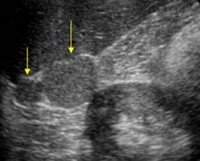

УЗИ брюшной полости помогает обнаружить дополнительные доли, если они имеют достаточный размер и не покрыты другими органами брюшной полости. В сложных диагностических случаях КТ также назначают при внутривенном введении контрастного вещества, что позволяет обнаруживать даже небольшие дополнительные образования.